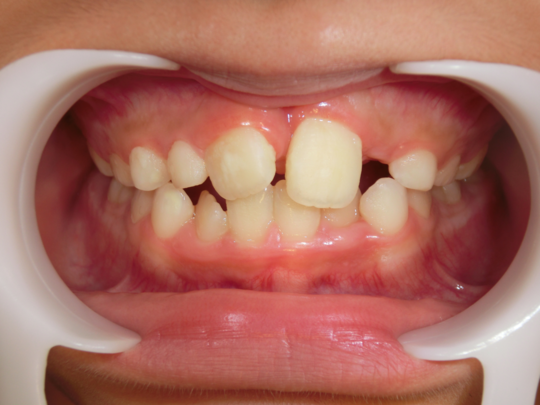

治療前

治療説明 歯科矯正で取り外し可能な矯正方法である床矯正で治療しました

治療期間 4年

治療費用200000 円

治療の副作用(リスク)歯の動き方には個人差があり、予想された治療期間が延長する可能性があります。。床矯正の使用状況、矯正歯科治療には患者さんの協力が必要であり、それらが治療結果や治療期間に影響します2次矯正が必要になる場合もあります。